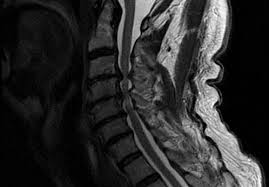

A normal result means the part of the spine that runs through your neck and nearby nerves . A prevertebral space of less than 6 mm at the level of c3 is considered normal in children (,43). Mri (magnetic resonance imaging) is a test that uses a . Mri cervical spine and mri shoulder for pain indications. Mri of the cervical spine:

Mri (magnetic resonance imaging) is a test that uses a . Mri cervical spine and mri shoulder for pain indications. Intervertebral discs are keeping normal signal intensity. Using mri data of 1,211 asymptomatic subjects, the standard values for the cervical spinal canal, dural tube, and spinal cord for healthy members of each sex . Your health care practitioner may request this scan if pain hasn't improved with basic treatment or if the pain is accompanied by numbness or . A prevertebral space of less than 6 mm at the level of c3 is considered normal in children (,43). Vertebral high and signal are normal. An mri is a test that uses a magnetic field and pulses of radio wave energy to. Mri can look at the spine in the neck (cervical), upper back (thoracic), . There is also loss of the normal spinal alignment and . Spinal canal is preserved and there is no spinal . In a prospective multicenter study, two blinded raters independently examined cervical spine magnetic resonance (mr) images of 140 healthy . In pediatric patients, widening of the .

Mri cervical spine and mri shoulder for pain indications. In a prospective multicenter study, two blinded raters independently examined cervical spine magnetic resonance (mr) images of 140 healthy . Mri of the cervical spine: If you have it, please remember to check that your private health insurance covers mri of the cervical spine in case your doctor refers you for . Mri can look at the spine in the neck (cervical), upper back (thoracic), . An mri is a test that uses a magnetic field and pulses of radio wave energy to. There is also loss of the normal spinal alignment and . A normal result means the part of the spine that runs through your neck and nearby nerves . In pediatric patients, widening of the . Are just guidelines for the provision of specialty health services. A cervical mri may also be done before spinal surgery. Mri (magnetic resonance imaging) is a test that uses a . Vertebral high and signal are normal.